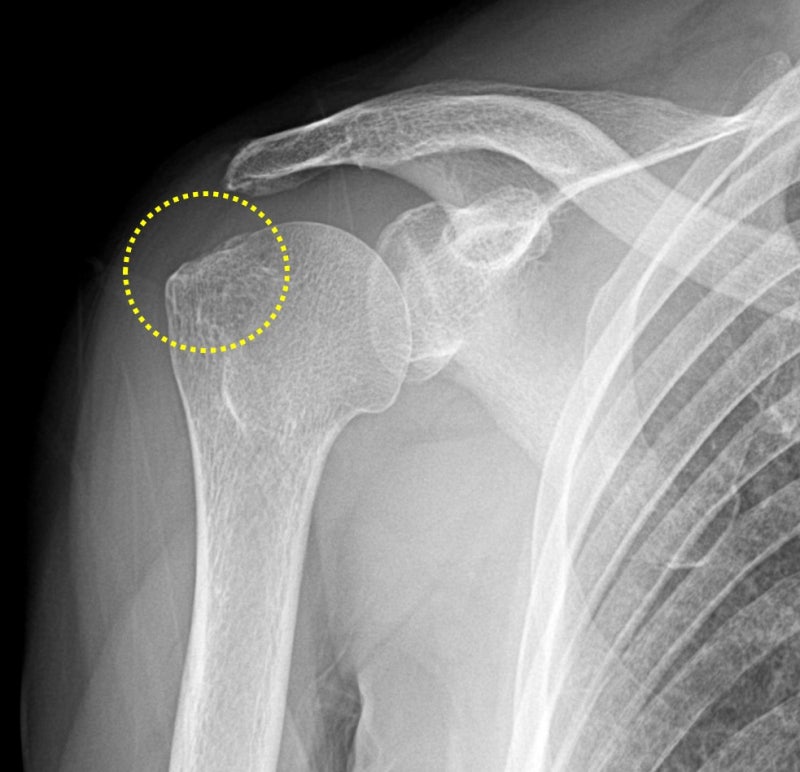

오늘은 회전근개 파열이 되고 너무 오래 되어서 완전히 해부학적으로 복원되지 않는 경우 인조인대(allomend)를 이용하여 해부학적으로 복원시킨 케이스를 살펴보도록 하겠습니다. 66세 여자 환자 분으로 오래전부터 어깨 통증이 있었는데 그냥 아플때만 주사맞으면서 견디셨다고 합니다. empty can test 양성 이었고 근력이 많이 떨어진 상태였습니다. X-ray 를 확인해 보았습니다.

이학적 검사나 x-ray 소견상 회전근개 파열이 상당히 많이 의심되어 MRI 검사를 시행하였습니다.